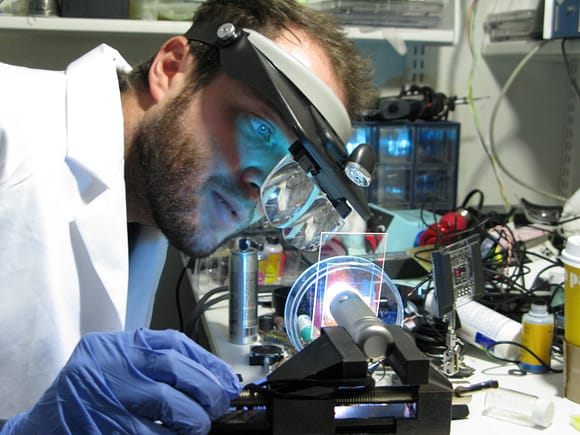

A cataract-affected eye scatters and refracts light before it reaches the retina, caused by a fogging or clouding of the lens. This system measures this deformation, or clouding, by allowing one to compare a good light path with a light path blocked by the cataract.

Current methods for cataract detection require costly equipment and highly trained clinicians. Traditional techniques measure back-scattering, which is observed and subjectively diagnosed, but do not address the early onset of cataract affected vision as early opacities are difficult to detect, especially in the field. Back-scattering can also be misleading as it does not account for what the patient actually sees. This novel approach, reduced here to practice, captures a full map of opacity and scattering, providing significant improvements beyond existing techniques which are limited to a simple grading of severity.